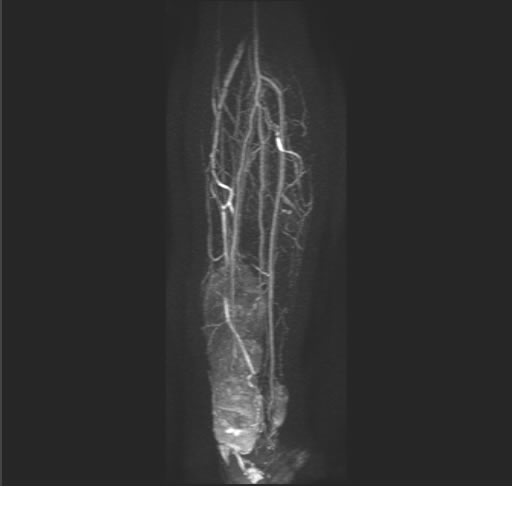

Se realiza estudio de MRI de pierna izquierda, utilizando secuencias Spin Echo y GRE en diferentes planos, se realiza angio MRI en fase arterial y venosa de pierna izquierda

El estudio demuestra masa a nivel de los músculos gemelos, más evidente en secuencia con pulso de saturación de grasa, en el estudio de angio resonancia de pierna la fase arterial no muestra ninguna anormalidad, en la fase venosa se observa acumulo del medio de contraste a este nivel.

Se concluye que se observa una masa de tejido muscular sumamente vascularizada compatible con un hemangioarcoma.